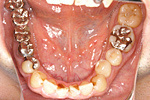

症例 11

① 左右の奥歯がありません。普通では左右つながった取り外しの入れ歯しか入りません。

② インプラントで固定式の義歯ができました。自分の歯に近い感じで食事ができます。

60才代 女性

総額:182万円(税別)

治療期間:6ヵ月

リスク副作用:メインテナンス不良ですと歯周炎、インプラント周囲炎になります。セラミックが欠けることがあります。